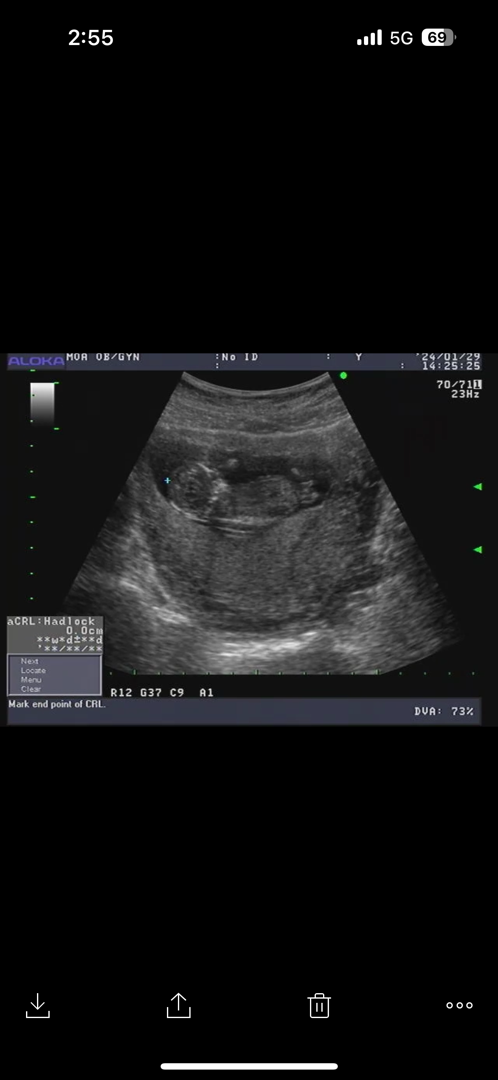

12주차 초음파 고수님들 봐주세여 ㅎㅎ

성별 혹시 봐주실수 잇나여~?ㅎㅎ12주차0일입니다